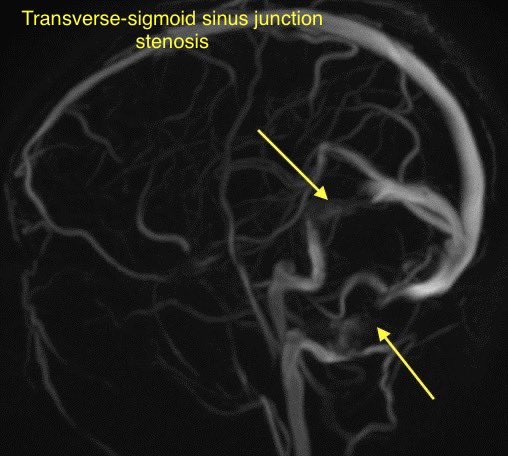

🔷TRANSVERSE SINUS STENOSIS & IDIOPATHIC INTRACRANIAL HYPERTENSION

🔸Intrinsic and extrinsic causes

INTRINSIC: Typically arachnoid granulations

🔹Arachnoid granulations may be incidental though they can produce IIH when obstructing a dominant transverse sinus or simultaneously blocking both

🔹Look for a round/lobulated filling defect with CSF signal on all images

EXTRINSIC: Defined as luminal narrowing with obtuse margins

🔹Typical cause of extrinsic stenosis is IIH though can occur without signs of IIH

🔹Tinnitus is present in up to 40-60% of patients with IIH (usually pulsatile and unilateral)

💡Bilateral transverse sinus stenosis is seen in 94% of patients with lIH

💡 Internal cephaloceles are another cause of extrinsic stenosis

💡 Stent placement is safe and effective in patients with transverse sinus stenosis (w/ or w/o lIH)